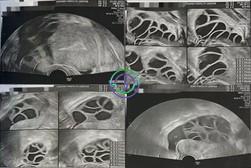

促排第 6 天 — LH 持续下降;卵泡反应增强

超声结果

右侧卵巢:卵泡大小 14, 13, 13, 12, 12, 11, 9, 9 mm → 共 8 个卵泡

左侧卵巢:卵泡大小 14, 14, 13, 13, 12, 12, 11, 11, 11, 9, 8, 8 mm → 共 12 个卵泡

激素结果

LH:6.2 mIU/mL

E2:843.2 pg/mL